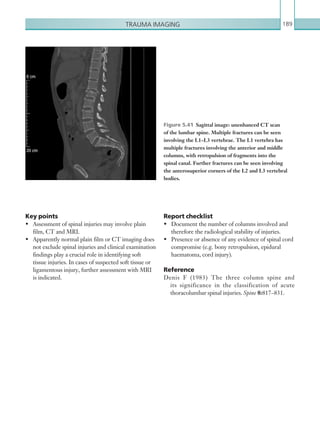

Interventional and ­vascularimaging and iatrogenic ­complications 195 Figure 6.6  PA chest radiograph. A nasogastric tube is seen passing into the left lower lobe bronchus. There is evidence of a left lower lobe pneumonia. Figure 6.7  Axial image: IV contrast enhanced CT scan of the thorax, which shows a significant left lower lobe pneumonia with a left lower lobe abscess, ­secondary to feeding via an incorrectly sited nasogastric tube (removed prior to imaging). ENDOTRACHEAL TUBE MISPLACEMENT A misplaced ET tube is a relatively common complication that is detected on post-intubation radiographs. If undetected, it can lead to respiratory complications and unnecessary morbidity and mortality. If the ET tube is too high, it can rub against the vocal cords and cause damage; if too low, it can selectively intubate the right or left bronchus, causing collapse of the contralateral lung. Table 6.3 Endotracheal tube misplacement. Imaging protocol. MODALITY PROTOCOL Plain film imaging PA chest X-ray to include the diaphragm. Radiological investigations Plain film imaging of the chest should be performed in all patients who have undergone ET tube placement. (See Table 6.3.) K22247_C006.indd 195 16/05/15 3:12 AM

• 218.

Chapter 6196 This isseen as dense opacification of the collapsed lung with volume loss, and mediastinal shift towards the collapsed lung. If the oesophagus has been intubated in error, gaseous distension of the stomach will be noted, with reduced lung volumes. Key points • A normal ET tube tip should lie 3–5 cm above the carina. • Intubation of a main bronchus can cause significant morbidity and the clinical team should be informed as a matter of urgency. Radiological findings Plain films A correctly placed ET tube tube should be seen in the midlinewiththetiplying3–5cmabovethecarina.Even when the carina is not visible, it can be assumed that a tip position overlying T3/T4 is safe. There can be considerable movement of the ET tube tip depending on the position of the neck, so accurate positioning can be difficult to determine. MisplacementoftheETtube,eithertooloworhigh, should be communicated immediately to the clinical team. If too low, there may be selective intubation of the right or left main bronchus, with corresponding collapse of the contralateral lung (Figures 6.8, 6.9). Figure 6.9  PA chest radiograph. The endotracheal tube in the same patient as in Figure 6.8 has been ­withdrawn to lie within the trachea and the left lung can be seen to have ­re-expanded. Figure 6.8  PA chest radiograph. An endotracheal tube is seen in the right main bronchus with almost complete collapse of the left lung. K22247_C006.indd 196 16/05/15 3:12 AM

• 219.

Interventional and ­vascularimaging and iatrogenic ­complications 197 ENDOVASCULAR STENT ENDOLEAK An endoleak is characterised by persistent blood flow within an aneurysm sac following endovascular aneurysm repair (EVAR). Normally, the aortic stent- graft used for EVAR excludes the aneurysm from the circulation by providing a conduit for blood to bypass the sac. Endoleaks are a common complication of EVAR and are found in 30–40% of patients intraoperatively (seen on the on-table angiogram after stent deployment) and in 20–40% during follow-up CTA imaging (Stavropoulos Charagundla, 2007). Endoleaks are often asymptomatic; however, they are significant as flow within the aneurysm sac is at high pressure and if untreated, the aneurysm sac may expand, leading to eventual rupture. As such, aneurysm expansion following EVAR always warrants investigation for endoleak. The causes of endoleak can be classified into five types (Table 6.4). Type I: Leak at graft attachment site: • Ia: proximal. • Ib: distal. Type II: Aneurysm sac filling via branch vessel: • IIa: single vessel. • IIb: two vessels or more. Type III: Leak through defect in graft: • IIIa: junctional separation of the modular components. • IIIb: fractures or holes involving the endograft. Type IV: Leak through graft fabric as a result of graft porosity. Type V: Continued expansion of aneurysm sac without ­demonstrable leak on imaging (endotension). Table 6.4  Classification of endoleaks. Table 6.5 Endovascular stent endoleak. ­Imaging protocol. MODALITY PROTOCOL CT Unenhanced. No oral contrast. Scan from just above diaphragm to the femoral heads. If a thoracic aortic endovascular stent ­endoleak is suspected, coverage of the thorax may suffice. Aortic angiogram: 100 ml IV contrast via 18G cannula, 4 ml/sec. Bolus track ­centred on mid-abdominal aorta. Scan from just above ­diaphragm to femoral heads. If a ­thoracic aortic endovascular stent ­endoleak is ­suspected, coverage of the thorax may suffice. Radiological investigations Ultrasound is usually used as a follow-up imaging modality to assess sac size and to check for the presence of an endoleak. It can also be used in the acute setting, but views may be limited as the quality of the images is user dependent. In the acute setting, the most accurate modality is CT.Thisenablestheradiologisttoaccuratelyassessthe sac size, confirm and characterise the endoleak as well as check for a leaking aneurysm. (See Table 6.5.) Radiological findings Computed tomography Baseline non-contrast CT imaging of the aorta is necessary to establish a baseline density within the aneurysm sac. Sometimes, the presence of calcification can mimic contrast and therefore alter the image interpretation. K22247_C006.indd 197 16/05/15 3:12 AM